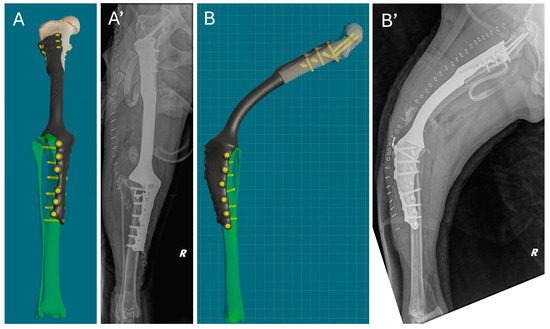

Immediately after surgery, a clinical assessment of joint stability and limb alignment was performed, and radiographs were taken in both standard orthogonal projections to assess the correct positioning of the implants and limb alignment. Correct implant positioning and limb alignment according to the preoperative plan were confirmed by the postoperative radiograph. (Figure 8).

Figure 8. Comparison of virtual surgical planning and postoperative radiographs. (A,A’) Cranial view. (B,B’) Lateral view.